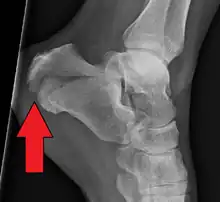

| X-ray of a fractured calcaneus | |

A calcaneal fracture is a break of the calcaneus (heel bone).[1] Symptoms may include pain, bruising, trouble walking, and deformity of the heel.[1] It may be associated with breaks of the hip or back.[1]

It usually occurs when a person lands on their feet following a fall from a height or during a motor vehicle collision.[2][1] Diagnosis is suspected based on symptoms and confirmed by X-rays or CT scanning.[1]